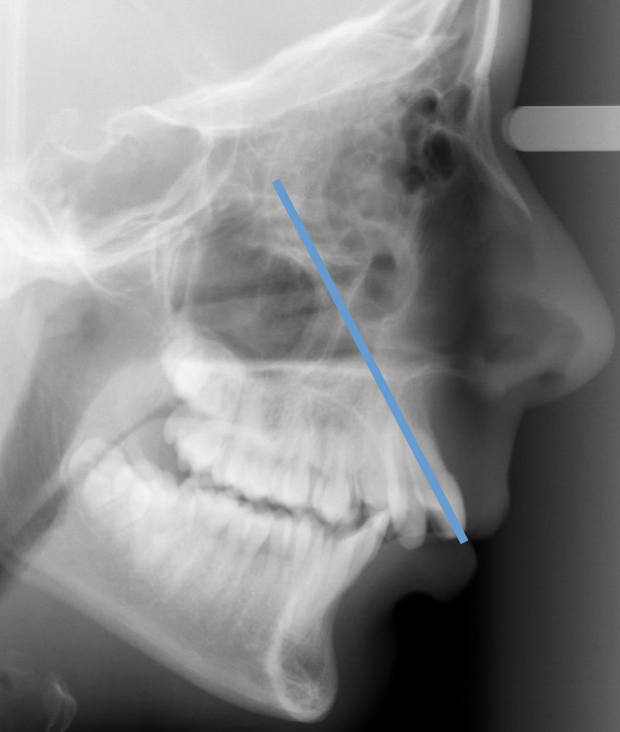

In the example, notice the blue lines. These indicate the relationship between the mesiobuccal cusp and mesiobuccal groove.

In a Class I occlusion, the mesiobuccal cusp of the maxillary first molar sits in the mesiobuccal groove of the mandibular first molar.

Class I occlusion is seen in 70% of malocclusions, and is the most common type of malocclusion.